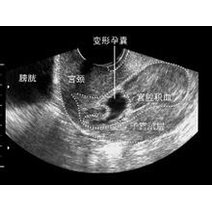

宫外孕的初期症状

初期怀孕HCG值对照表及注意事项: 1.HCG正常范围:孕1周5-50mIU/ml,2-3周100-5000mIU/ml,3-4周可达数千mIU/ml。 2.HCG变化意义:4周左右翻倍增长提示发育良好,增长缓慢或过快可能提示异常...

HCG值在100~5000mIU/ml左右;3~4周时,HCG值在500~10000mIU/ml左右;4~5周时,HCG值在1000~50000mIU/ml左右;5~6周时,HCG值在10000~100000mIU/ml左右;6~8周时,HC 怀孕初期HCG值对...